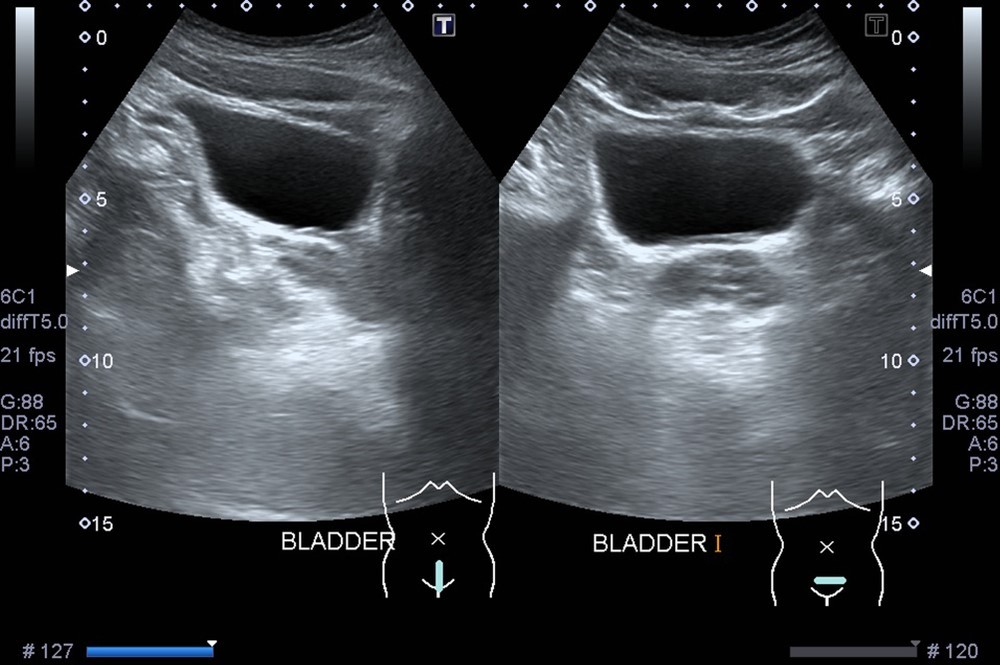

Ультразвук обеспечивает четкое изображение стенок органа, формы, размера и наличия каких-либо отклонений. Его можно выполнить двумя основными вариантами: трансабдоминально (через низ живота) и внутренним доступом (через влагалище у женщин). Трансабдоминальный подход используется чаще и особенно полезен для оценки объема остаточной мочи и наполненного пузыря.

- Визуализация после мочеиспускания: после получения первоначальных изображений пациента могут попросить опорожнить мочевой пузырь, и будут сделаны дополнительные изображения для измерения оставшейся мочи.